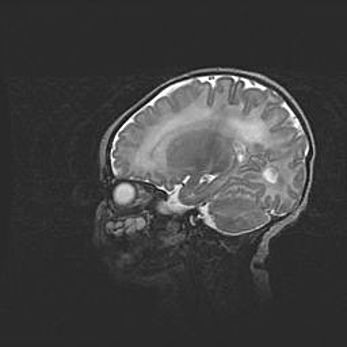

Аномалия Денди-Уокера. Признаки гипоплазии мозолистого тела.

Возраст: 5 месяцев 3 дня

Вес: 5550 г

Пол: мужской

Окружность головы: 39 см

Срок гестации: 40 недель

Аномалия Денди-Уокера – это порок развития головного мозга, для которого характерна триада симптомов: гипотрофия или аплазия червя мозжечка и/или полушарий мозжечка, расширение четвёртого желудочка с формированием ликворной кисты задней черепной ямки, гипертензионная гидроцефалия различной степени.

Гипоплазия мозолистого тела относится к дефектам внутриутробного этапа развития мозговой ткани, возникающим в процессе закладки структур головного мозга, что происходит на начальных этапах развития эмбриона.